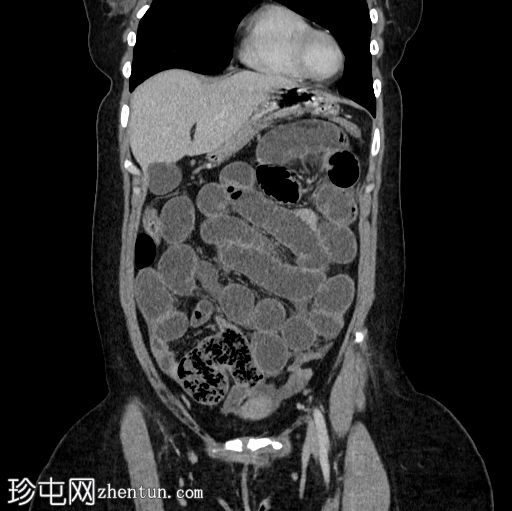

矢状位增强扫描(门静脉期)

小肠袢扩张,远端回肠袢可见粪便样改变,提示移行点就在附近。移行点远端可见回​​肠塌陷。

在移行点近端,肠系膜对侧缘可见一盲端管状结构,符合梅克尔憩室的特征。

少量游离液体。